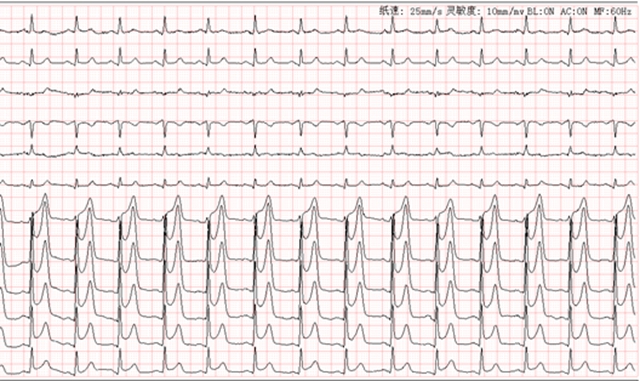

同行的朋友见他脸色惨白、嘴唇发紫,赶紧拨打了120急救电话。送到西南医科大学附属中医医院后,心电图检查结果显示为广泛前壁急性心肌损伤性改变。

(心电图显示可见V1-V6导联ST段上斜型抬高0.35-.0.85vm,正常情况下V1-V6导联ST段抬高不应该>0.2vm,显然陈先生的病情已经相当严重了,这是冠状动脉急性闭塞的典型表现)。

心电图作为一种无创、迅速且经济的诊断工具,在心肌梗死的早期诊断中扮演着至关重要的角色。心电图能够在心肌梗死早期(症状发作后的数分钟至数小时内)捕捉到特征性的ST-T改变和病理性Q波,为早期诊断提供关键依据。